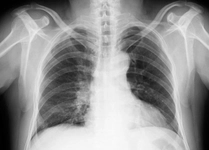

Akciğer tansiyonu, pulmoner hipertansiyon olarak da bilinen bu durum, akciğerlerdeki kan damarlarının basıncının normalden daha yüksek olması anlamına gelir. Bu rahatsızlık, kalp ve akciğer fonksiyonlarını etkileyebilir ve ciddi sağlık sorunlarına yol açabilir. Bu makalede, akciğer tansiyonunun insan sağlığı üzerindeki etkileri, belirtileri, nedenleri ve tedavi yöntemleri detaylı bir şekilde ele alınacaktır. Akciğer Tansiyonu Nedir?Akciğer tansiyonu, akciğerlerdeki kan damarlarındaki basıncın yükselmesi sonucu ortaya çıkar. Normalde, akciğerlerdeki kan damarlarının basıncı 8-20 mmHg arasında olmalıdır. Ancak bu değerlerin üzerinde bir ölçüm, pulmoner hipertansiyon olarak kabul edilir. Akciğer tansiyonu genellikle, kalp sağlığı üzerinde de olumsuz etkiler yaratır. Akciğer Tansiyonunun BelirtileriAkciğer tansiyonu, birçok belirti ile kendini gösterebilir. Bu belirtiler, hastalığın şiddetine göre değişiklik gösterebilir. Yaygın belirtiler şunlardır:

Akciğer tansiyonu, pulmoner hipertansiyon olarak bilinir ve akciğerlerdeki kan damarlarının basıncının yükselmesi durumudur. Bu durum, kalp sağlığını doğrudan etkileyebilir çünkü kalbin sağ ventrikülü, akciğerlerden gelen kanı pompalamak için daha fazla çalışmak zorunda kalır. Uzun vadede bu durum kalp yetmezliğine yol açabilir.